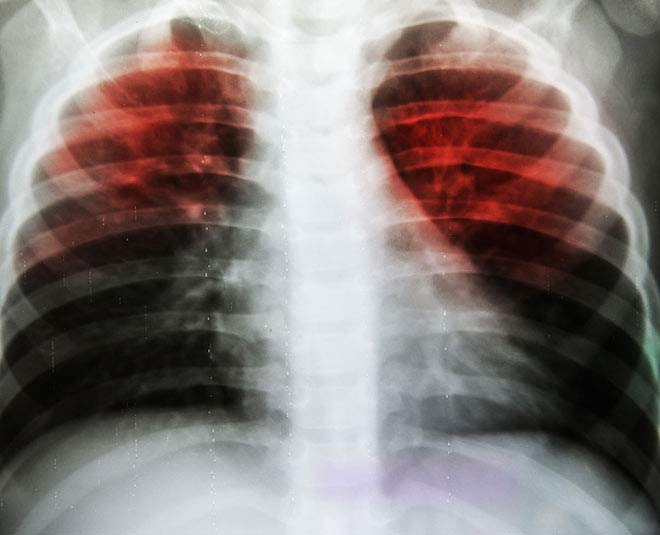

सोमवार को विश्व स्वास्थ्य संगठन (डब्लूएचओ) द्वारा टीबी रिपोर्ट 2017 जारी की है। दुनिया भर में सबसे ज्यादा टीबी के मामले भारत में है। 2016 में सबसे ज्यादा टीबी के मामले भारत में सामने आए इसके बाद इंडोनेशिया, चीन, फिलीपींस और पाकिस्तान हैं।

विश्व स्वास्थ्य संगठन (डब्ल्यूएचओ) की रिपोर्ट के अनुसार, 2016 में दुनिया भर में ट्यूबरकुलोसिस (टीबी) के 1.04 करोड़ नए मामले सामने आए, जिसमें 64 फीसदी के साथ सात देशों में भारत पहले नंबर पर है। इसकी वजह से भारत में 2016 में 4.23 लाख मौतें हुई हैं। 2025 तक भारत टीबी मुक्त होने की महात्वाकांक्षी योजना है लेकिन इस रिपोर्ट में भारत की स्थिति चिंताजनक है।

डब्ल्यूएचओ की रिपोर्ट में कहा गया है, "भारत में टीबी अनुमान की तुलना में कही अधिक बड़ी महामारी है। यह निगरानी और सर्वेक्षण के नए आंकड़ों से पता चला है।"